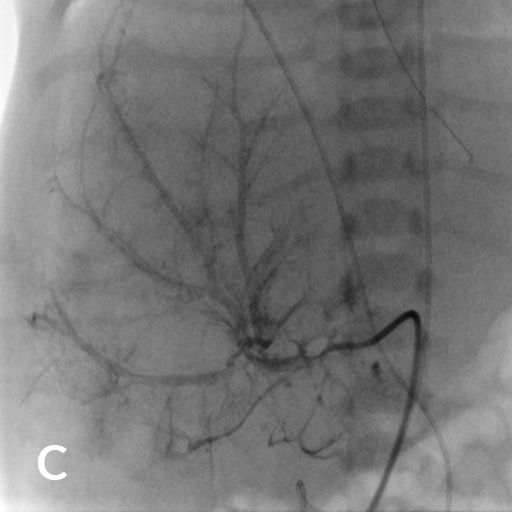

7 jähriger Junge mit Kurzdarmsyndrom und Leberzirrhose

Als Folgen des Pfortaderhochdrucks war die Milz vergrößert (Splenomegalie) und es traten Krampfadern der Speiseröhre (Ösophagusvarizen) auf. Um den Hochdruck zu entlasten wurde ein TIPS angelegt. Dazu wird aus der rechten Lebervene (A) mit einer speziellen Nadel ein Pfortaderast punktiert (B). Anschließend wird die Pfortader mit einem Draht sondiert (C) und die geschaffene Verbindung mit einem Ballon aufgedehnt und anschließend mittels Gefäßstütze (Stent) geschient (D). Durch diese künstliche Verbindung kann das Pfortadersytem deutlich druckentlastet werden.